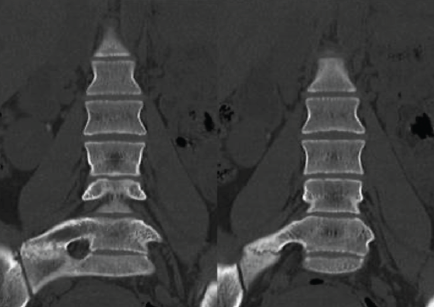

X-rays (Fig. 2), CT scan (Fig. 3), and MRI revealed a LVT with a right hypertrophic transverse process at L5, which articulated with the sacrum and was compatible with Castellvi type IIa. SPECT findings indicated focal hypercaptation within the pseudoarticulation, suggesting symptomatic focus (Fig. 4).

Figure 4: Single-photon emission computed tomography-computed tomography of the lumbosacral region: Focal area of increased uptake at the pseudoarticulation between the right L5 mega-transverse process and the sacrum in the coronal (a), axial (b), and sagittal (c) views.